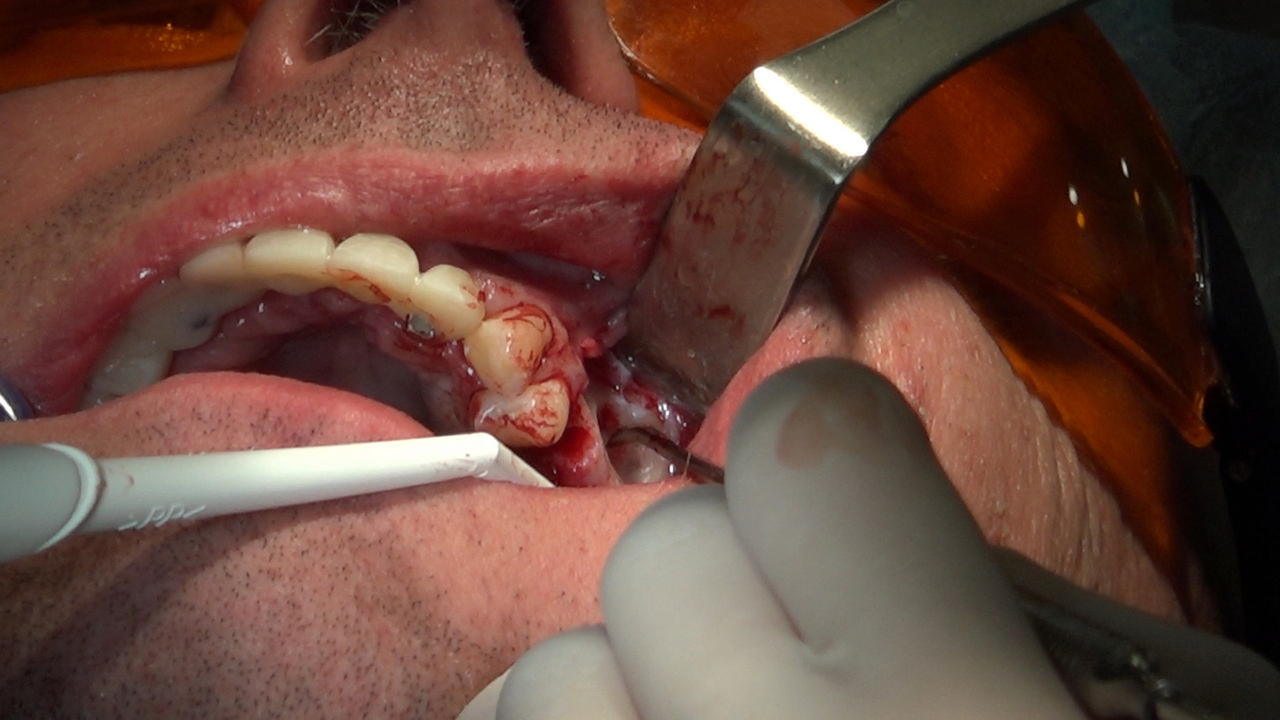

7 Sesja X Sezonu Practiculum Implantologii, w której brali udział kursanci z Grupy A i B, obejmowała implantacje wykonane systemem Axiom, procedury regeneracyjne tkanki kostnej i zabieg sinus lift oraz procedury implantoptotetyczne. Ten zakres szkolenia poprowadziła dr Małgorzata Piotrowska. Protetyka na implantach, to finalny etap leczenia implantologicznego decydujący o uzyskaniu harmonijnego łuku zębowego, okluzji oraz szczelności połączeń, a więc zadowoleniu Pacjenta i powodzeniu całego procesu leczenia.

Jego sednem jest wybór optymalnego rozwiązania rekonstrukcji protetycznej uwzględniający bardzo wiele czynników o charakterze mechanicznym, funkcjonalnym i estetycznym, związanych ze stanem tkanki kostnej, jamy ustnej i uzębienia. Odbywa się już na etapie tomografii komputerowej i jest ściśle powiązany z częścią chirurgiczną, ponieważ prawidłowe zaplanowanie pracy i usytuowania implantów wspomagane plastyką tkanek miękkich, to dla procedur protetycznych baza wyjściowa. Zasady te są jak najbardziej oczywiste, zarówno przy samodzielnym wykonywaniu leczenia implantologicznego, jak i przy podziale zadań dla chirurga i protetyka, czyli pracy w duecie.